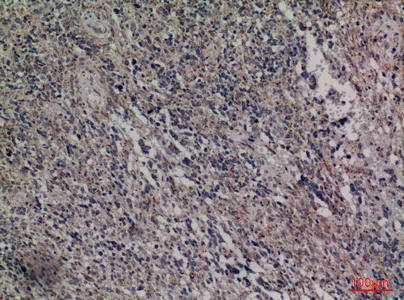

HDC Rabbit Polyclonal Antibody

Cat: APRab11956

Size1:50μl Price1:$118

Size2:100μl Price2:$220

Size3:500μl Price3:$980